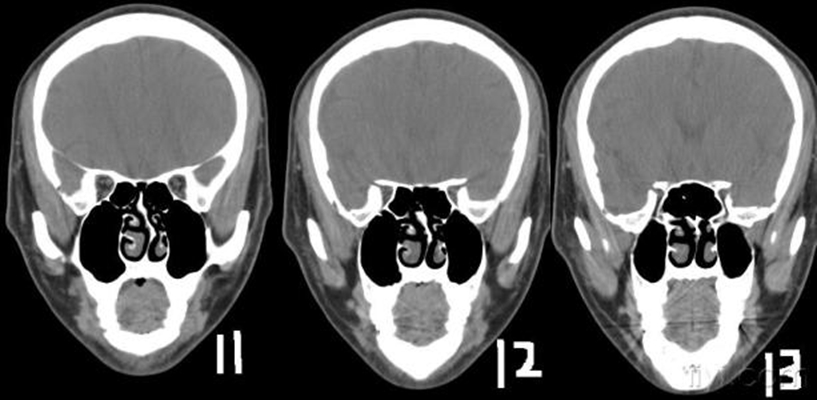

鼻中隔偏曲圖片

鼻中隔彎曲手術圖解 (7)